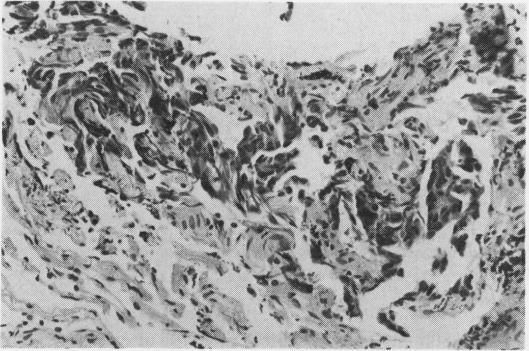

A 67-year-old man presented to the pulmonary service with left shoulder and arm pain. Examination disclosed a left Horner's syndrome. Supraclavicular exploration at another hospital was not helpful. Transbronchial biopsy through a flexible fibreoptic bronchoscope retrieved tissues showing poorly differentiated carcinoma. There are no previous reports of the use of the technique in the diagnosis of a Pancoast tumour with a normal standard chest radiograph.

一名67岁男性因左肩和手臂疼痛就诊于肺部专科。检查发现左侧霍纳综合征。在另一家医院进行的锁骨上探查并无帮助。通过可弯曲纤维支气管镜进行经支气管活检获取的组织显示为低分化癌。此前尚无关于在标准胸部X线片正常的情况下使用该技术诊断潘科斯特瘤的报道。